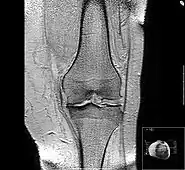

Diagnosis is made with reasonable certainty based on history and clinical examination.[51][52] X-rays may confirm the diagnosis. The typical changes seen on X-ray include: joint space narrowing, subchondral sclerosis (increased bone formation around the joint), subchondral cyst formation, and osteophytes.[53] Plain films may not correlate with the findings on physical examination or with the degree of pain.[54]

Joint injection of glucocorticoids (such as hydrocortisone) leads to short-term pain relief that may last between a few weeks and a few months.[110] A 2015 Cochrane review found that intra-articular corticosteroid injections of the knee did not benefit quality of life and had no effect on knee joint space; clinical effects one to six weeks after injection could not be determined clearly due to poor study quality.[111] Another 2015 study reported negative effects of intra-articular corticosteroid injections at higher doses,[112] and a 2017 trial showed reduction in cartilage thickness with intra-articular triamcinolone every 12 weeks for 2 years compared to placebo.[113] A 2018 study found that intra-articular triamcinolone is associated with an increase in intraocular pressure.[114]

Hyaluronic acid